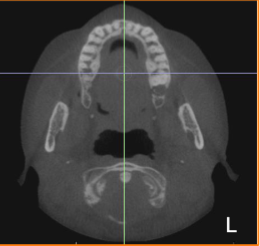

axial

what plane is this